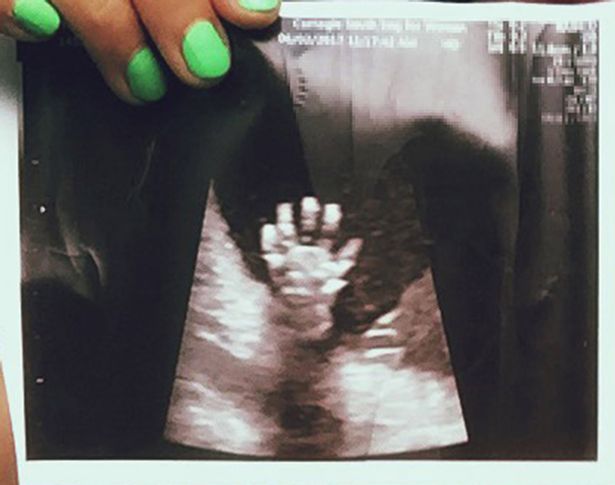

Old  Default Mẹ kinh ngạc thấy con giơ tay “high-five” trong lúc siêu âm

Vietbf.com - Bà mẹ kinh ngạc khi xem bức ảnh siêu âm bầu thai của mình 20 tuần, lại thấy con giơ 5 ngón tay hình như muốn “high-five” (đập tay) với mẹ, khiến cặp vợ chồng đăng bức ảnh này lên mạng xã hội và nó lan truyền thật nhanh chóng.

Libby cầm bức ảnh siêu âm lúc mang thai 20 tuần

Trong lần siêu âm ở tuần thứ 20, cặp đôi vô cùng ngạc nhiên khi nhìn thấy con gái giơ cả bàn tay lên, xòe ra 5 ngón. Cặp vợ chồng đăng bức ảnh này lên mạng xã hội và nó lan truyền nhanh chóng, theo Mirror.

Bé gái giơ cả bàn tay lên, xòe ra 5 ngón